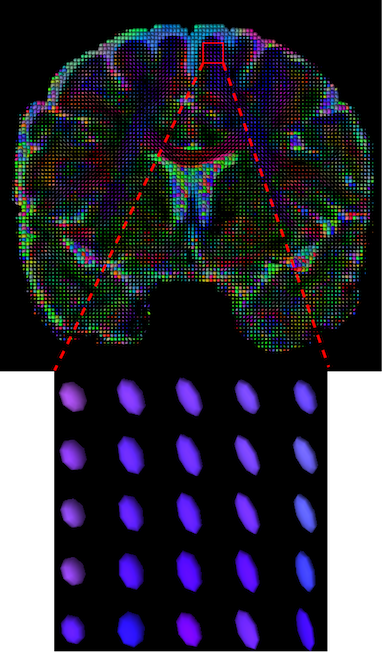

The visualization of inpainted results (showing the whole diffusion tensor for each voxel) generated from different models are demonstrated in Figure 3, where the tensor is represented in RGB coding that colours red, green and blue represent diffusion in the x, y, and z axes respectively. One typical example of reconstruction in the disrupted ROIs has been zoomed for visualization. Compared to the ground truth, TW-BAG is able to generate more distinct orientations following the original distribution and intensity across sagittal, coronal and axial views, which could demonstrate water diffusivity (denoted by eigenvalues of tensor model) more accurately. As indicated in Figure 4, the boundaries and textures of the FA map for TW-BAG are less blurry than the other competing models, validating the effectiveness of TW-BAG from a neuroscience perspective.